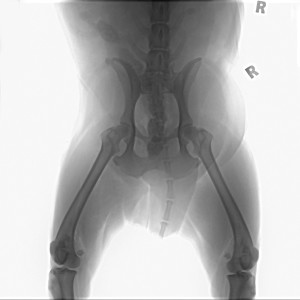

It just happened to me. Sobek, my Rottweiler, was gleefully playing outside and the unexpected happened. He yelped and refused to put weight on his left rear leg. After an ER visit, it was confirmed. Cranial cruciate ligament tear. Darn!

When Sobek partially tore his cruciate ligament, I contacted several board certified veterinary orthopedic surgeons. Every one of them stated that CM provides best results for dogs under 30 pounds and older dogs with lower energy levels. I’ve read of several large dogs healing fine with 6-8 months of CM. This is your decision. Personally, I would rather do CM over surgery any day, but Sobek is young, has high energy and weighs 120 pounds.